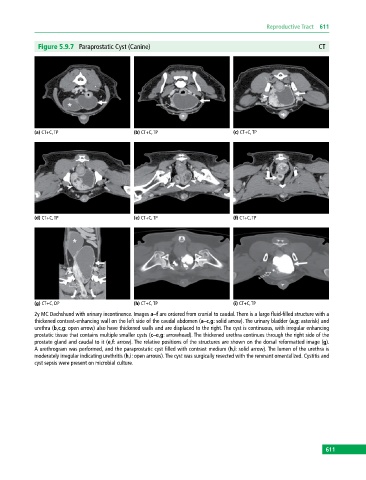

Figure 5.9.7 Paraprostatic Cyst (Canine) CT

(a) CT+C, TP (b) CT+C, TP (c) CT+C, TP

(d) CT+C, TP (e) CT+C, TP (f) CT+C, TP

(g) CT+C, DP (h) CT+C, TP (i) CT+C, TP

2y MC Dachshund with urinary incontinence. Images a–f are ordered from cranial to caudal. There is a large fluid‐filled structure with a

thickened contrast‐enhancing wall on the left side of the caudal abdomen (a–c,g: solid arrow). The urinary bladder (a,g: asterisk) and

urethra (b,c,g: open arrow) also have thickened walls and are displaced to the right. The cyst is continuous, with irregular enhancing

prostatic tissue that contains multiple smaller cysts (c–e,g: arrowhead). The thickened urethra continues through the right side of the

prostate gland and caudal to it (e,f: arrow). The relative positions of the structures are shown on the dorsal reformatted image (g).

A urethrogram was performed, and the paraprostatic cyst filled with contrast medium (h,i: solid arrow). The lumen of the urethra is

moderately irregular indicating urethritis (h,i: open arrows). The cyst was surgically resected with the remnant omentalized. Cystitis and

cyst sepsis were present on microbial culture.